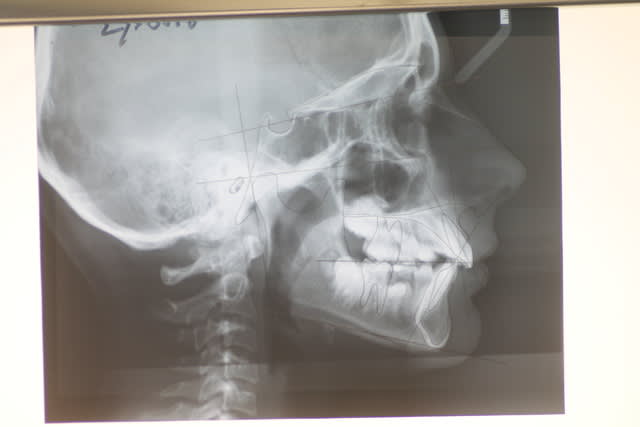

Il faudrait plus d'éléments pour répondre ( télé profil, pano, photos endo et exo buccales)

Si il s'agit d'une classe II.2 :

- le condyle se retrouve très souvent en rétro position forcée à cause de l'inclinaison des incisives maxillaires

- dans une luxation discale : le disque se retrouve "en avant" du condyle

- le patient étant en classe II, en cours de croissance, il y a tout intérêt à essayer de le faire propulser, au lieu de "distaler" les molaires maxillaires ( encore un mythe...)

quelques documents :